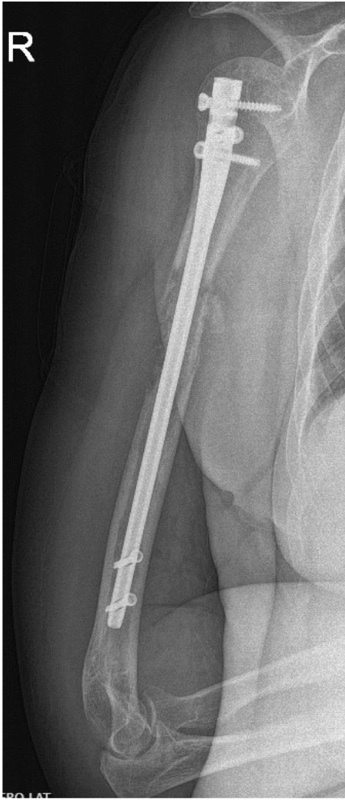

La stabilizzazione preventiva o su frattura mediante intervento di infibulo endomidollare deve sempre osteosintetizzare (o stabilizzare) l’intero segemento ed è riservata a pz con scarsa prognosi in cui permette un rapido sollievo dal dolore e ripresa della funzionalità (Fig. 2).

Deve essere associata sempre a radioterapia post-operatoria. Le localizzazioni metafisarie possono essere controllate meglio con intervento di curettage e placca dopo riempimento con cemento (Fig.3 a-d). La cementoplastica è emersa come una promettente opzione clinica, sicura e fattibile soprattutto per le sedi più complesse come l’acetabolo26.